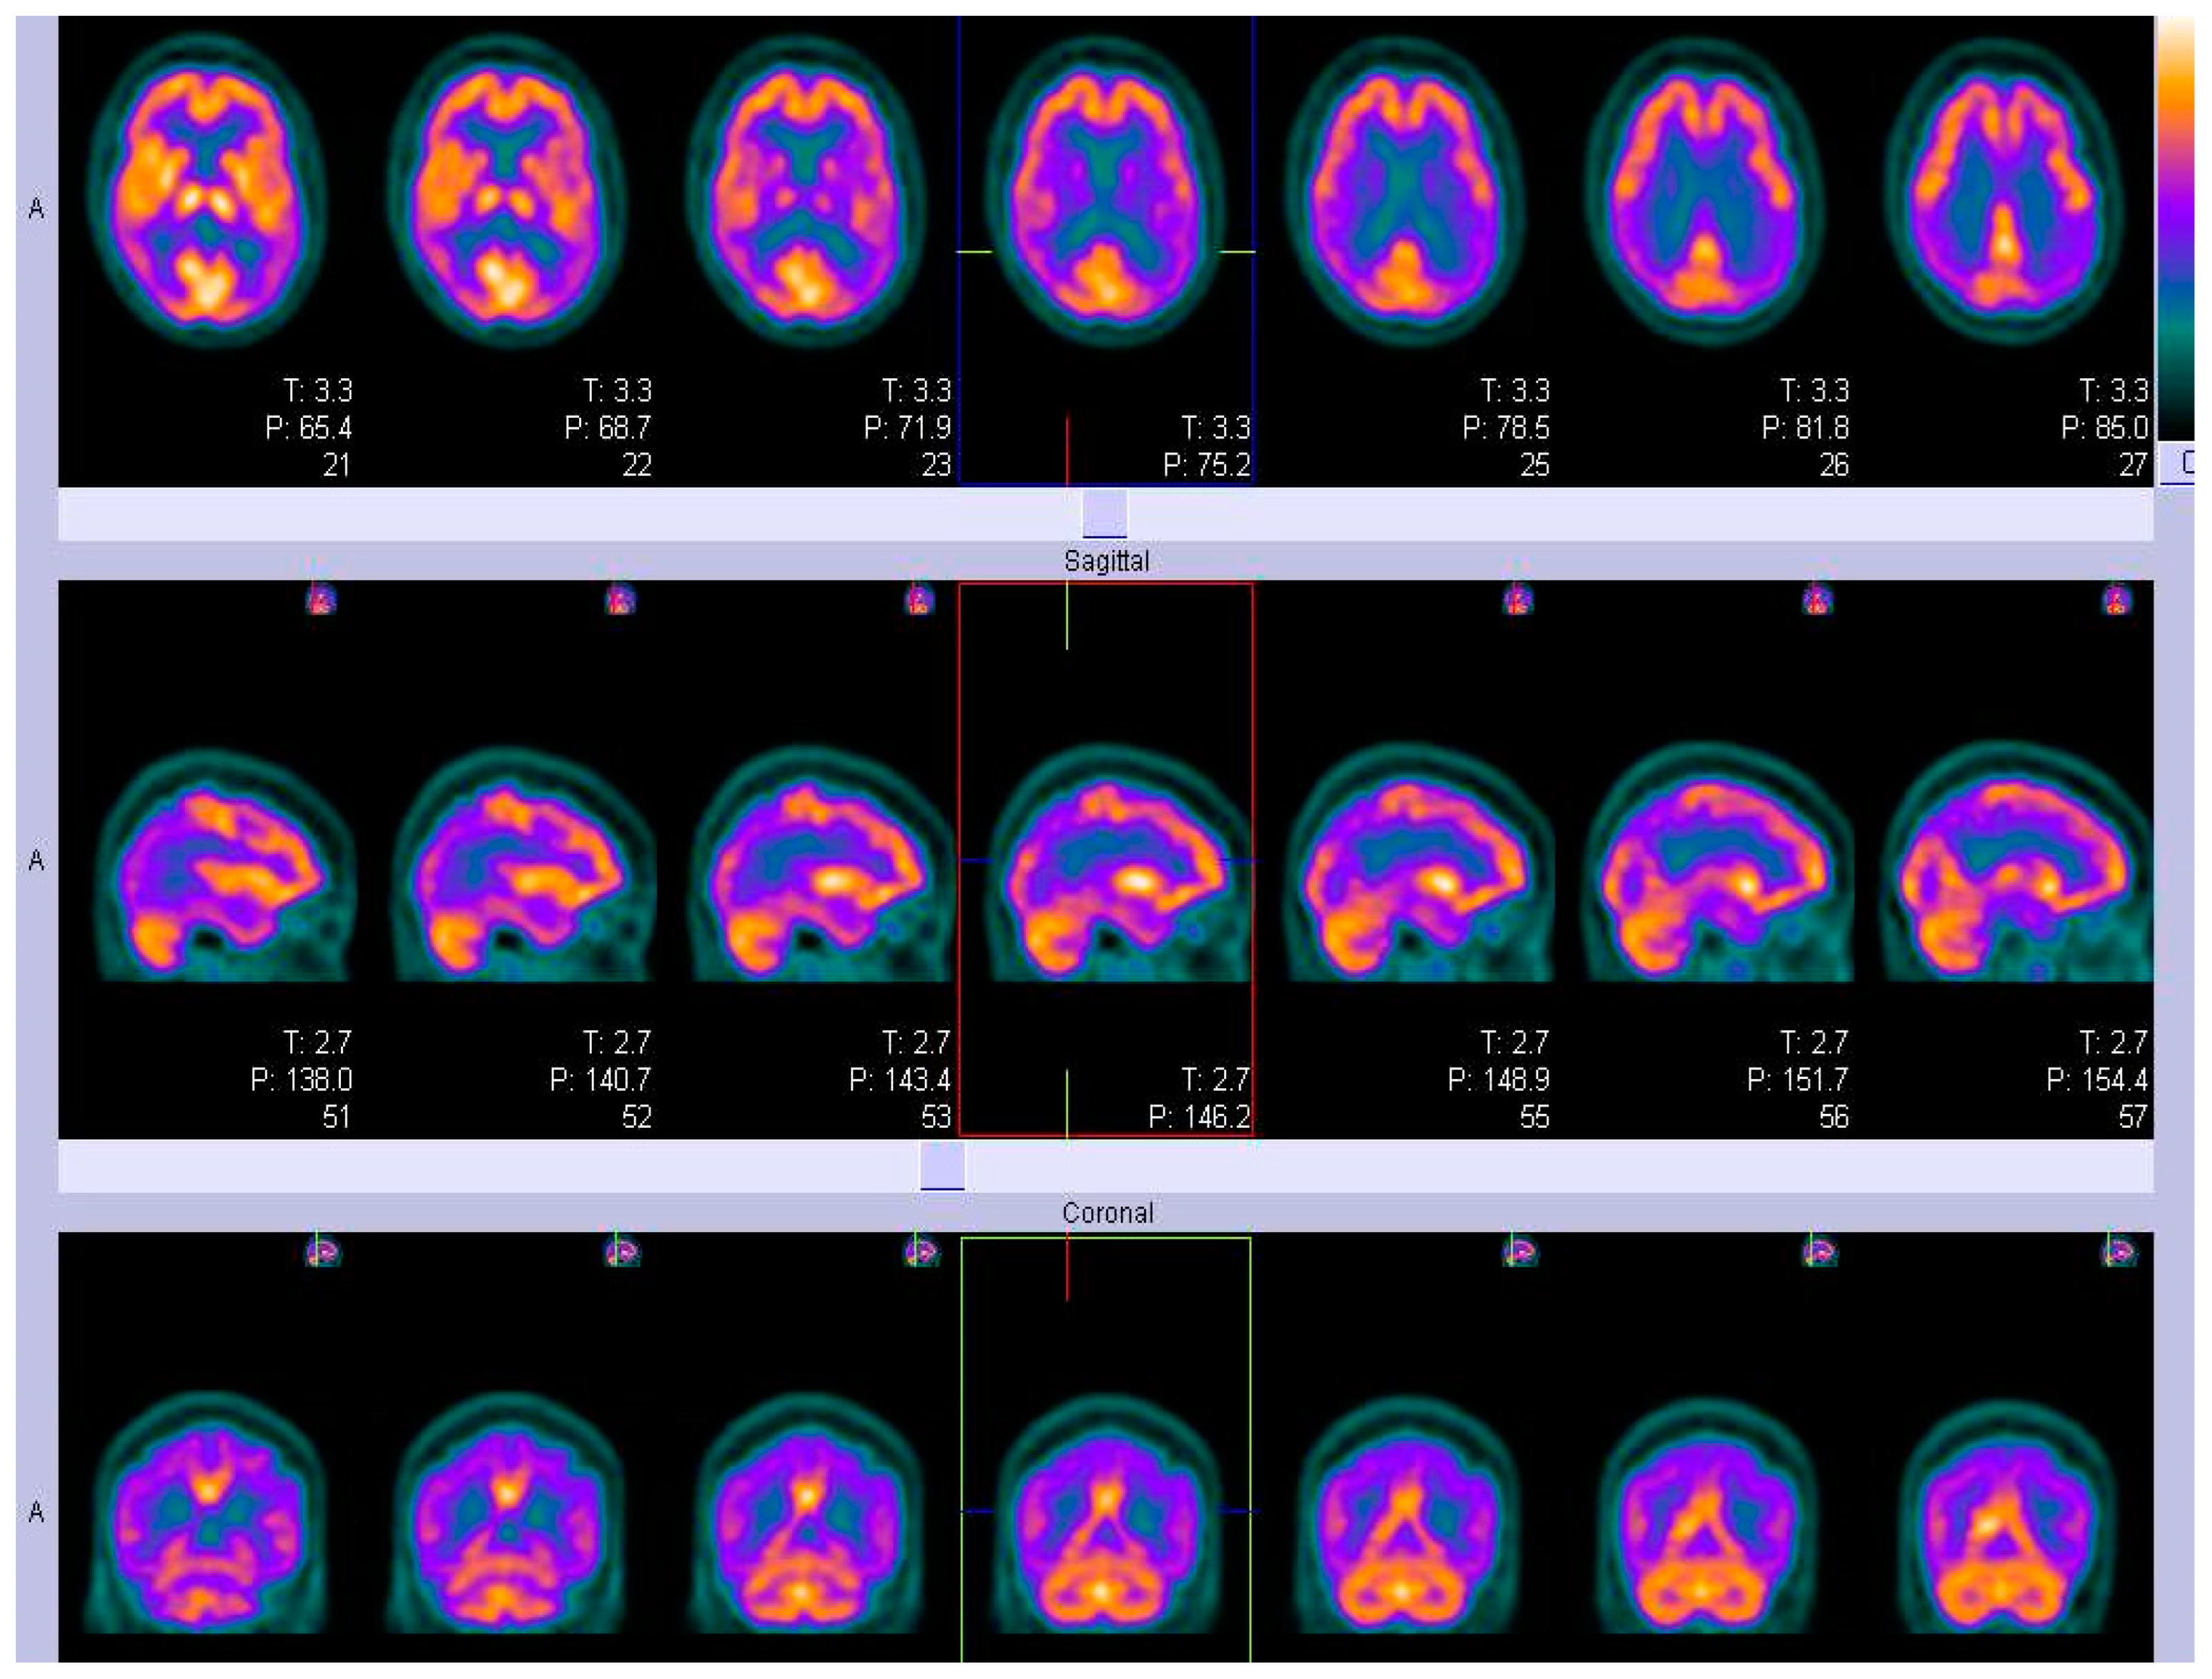

FDG-PET

SPECT

ECD and HMPAO- SPECT